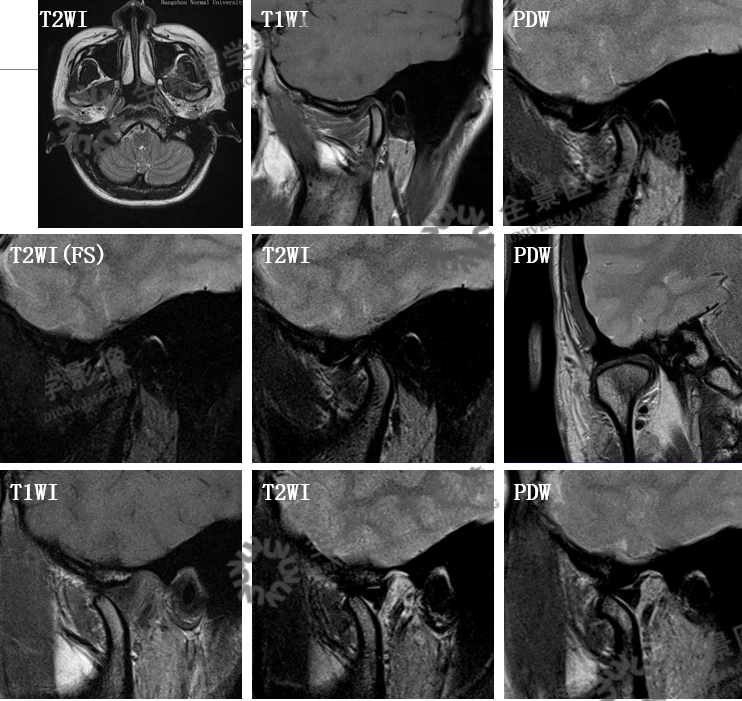

一、颞颌磁共振检查

概述

针对疾病:颞下颌关节紊乱病(TMD)

MRI:可清楚、全面地反映关节结构及附件组织的变化。MR动态电影能够很好地显示关节盘、髁状突的运动情况

颞颌磁共振检查